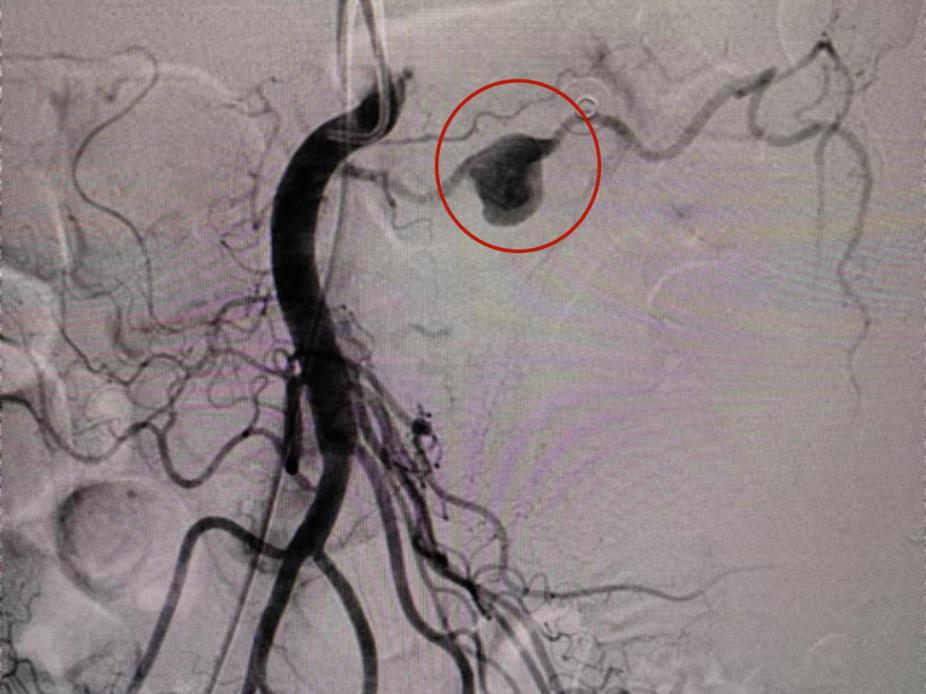

经过CT检查后发现

张大伯的一侧肾脏有包块

且腹腔内也出现了大量积液(血)

约有1000mL

手术治疗迫在眉睫

介入科主任侯国欣、副主任医师刘磊等第一时间为张大伯实施介入栓塞术,对出血点进行快速栓塞。